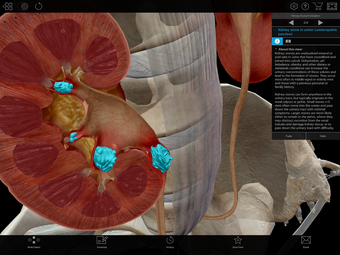

Physiology & Pathology is a comprehensive application that provides an interactive guide to human anatomy. Developed by Visible Body, this Android application is a full version licensed program that falls under the lifestyle category of medical subcategories. With more than 5,800 3D models, 38 animations, 16 illustrations, and 26 quizzes, this application covers 48 physiology topics and 57 conditions, allowing users to explore the step-by-step breakdown of common cardiovascular, renal, respiratory, gastrointestinal, and musculoskeletal processes.

One of the most remarkable features of this application is that it enables users to compare 3D models of normal anatomy with models of common diseases and conditions. Furthermore, users can set the heart rate and visualize conduction in a dissectable, beating 3D heart while following along on an ECG. The application also presents animations that demonstrate the physiological processes of gas exchange, pulmonary ventilation, fluid balance, peristalsis, and more. Interactive lessons walk users through the progression of atherosclerosis, kidney stones, lung cancer, and other common conditions, and quizzes test users' knowledge of various physiological processes and pathologies.